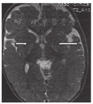

3.2 胆红素脑病对于疑有胆红素脑病的婴儿,在急性期,苍白球内T1WI信号强度的增加明显,T2WI增加较T1WI不明显(图6)[7]或不增加。到6个月后,在T2WI上异常信号变得更加明显,T1WI上信号强度降低。胆红素脑病经典的头颅MRI后期表现:T2WI在苍白球区显示高信号强度(图7)[8],还可累及到丘脑底核和海马等。

图6

胆红素脑病急性期 A:T1加权像:苍白球内信号强度增加明显(箭头所示);B:T2加权像:信号强度增加不明显(箭头所示)

Figure 6

Nuclear jaundice A:T1 weighted image showing subtle but clear increased T1 signal intensity in the globus pallidum bilaterally (arrow showed);B:T2 weighted image showing unremarkable T2 signal intensity in the globus pallidum bilaterally(arrow showed)